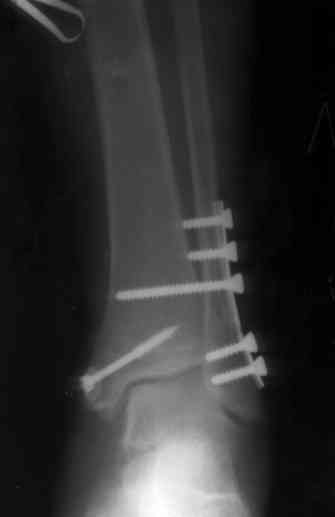

Здесь финальный снимок 73 летней с

сопутствующей шизофренией, латерально бридж

пластину (соединили дистальный конец с диафизом не трогая место перелома) и медиально перкутанно

двумя шурупами. В этам случае без гипса не

обойтись.

Джолдас, Здравствуйте,

Красивые Рг-граммы! У меня нет опыта перкутанной фиксации внутренней лодыжки, поэтому интересно узнать, наблюдали ли вы несращения внутр.лодыжки